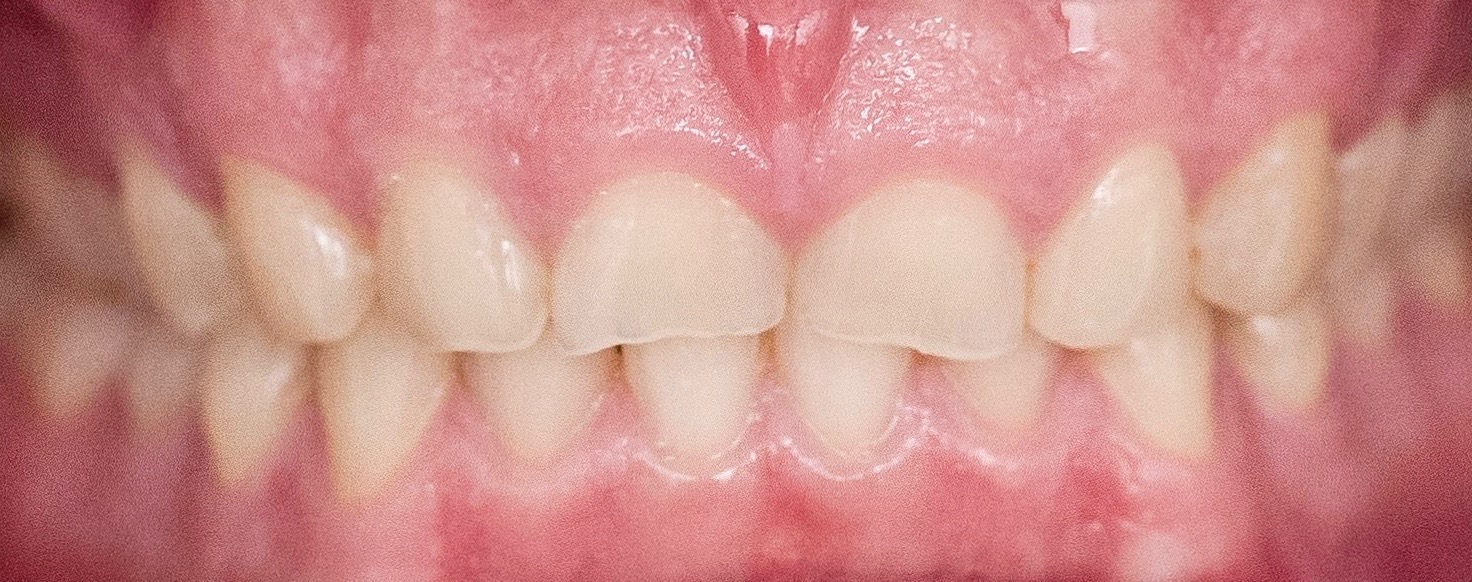

Digital impressioning and digitally driven treatment planning and execution are quickly becoming the norm in orthodontic treatment. This allows for interdisciplinary treatment to be performed digitally, even in the presence of brackets and wires. As an example, a 13-year-old patient presented with congenitally missing maxillary lateral incisors, as well as tooth No. 22. After discussing various treatment options, the patient and her parents decided to maintain the edentulous spaces with resin-bonded fixed partial dentures (RBFPDs) until the patient was old enough for dental implants. At completion of orthodontic treatment but before removal of brackets and wires, the patient was digitally scanned (Figure 18). Her models were manipulated in orthodontic software to remove the brackets, and the case was imported into restorative CAD software for design and fabrication of the RBFPDs (Figure 19). The e.max RBFPDs were milled and subsequently delivered immediately after bracket removal (Figure 20).

Fig 18. Scans of patient while still in orthodontic brackets.

Figure 18